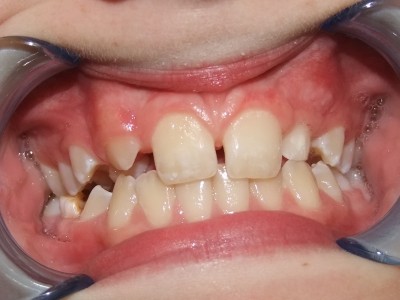

Voor behandeling